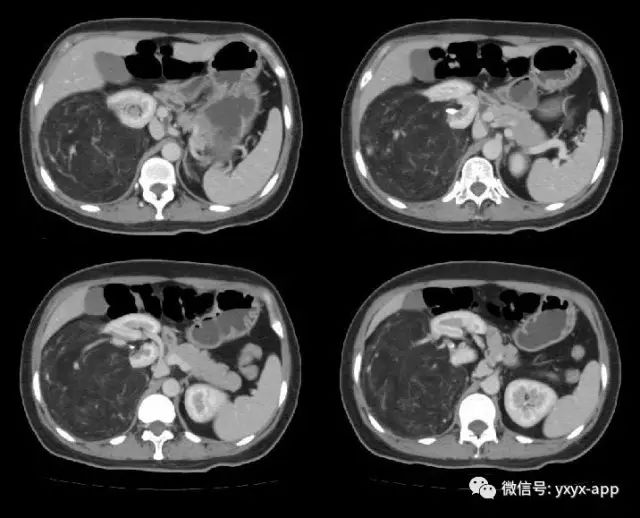

肚肚丫头:右肾中极肾皮质欠完整,呈喇叭口样改变,并可见突出肾脏轮廓的巨大脂肪密度影,其内信号欠均匀,病变边界清楚,周围脏器未见异常密度影及受侵征象,增强扫描病变呈欠均匀较显著强化,腹膜后未见肿大淋巴结。考虑来源于肾脏的含脂肿瘤占位病变,右肾巨大血管平滑肌脂肪瘤可能。鉴别诊断:1. 肾周脂肪肉瘤;2. 腹膜后脂肪瘤/高分化脂肪肉瘤;3. 肾上腺髓质脂肪瘤; 4. 腹膜后畸胎瘤。

【病理结果】肾脏血管平滑肌脂肪瘤

血管平滑肌脂肪瘤是肾脏最常见的良性肿瘤,病理上由平滑肌、脂肪细胞和异常血管混合组成,它们的含量差别较大,多数以脂肪成分为主,少数以平滑肌为主。好发于中年女性,大多数为单侧单发,少数为双侧多发。临床表现主要有肾区疼痛,可有血尿及腹部包块,少数临床上无任何不适症状,体检时偶然发现。

CT 诊断主要根据肿瘤内脂肪成分的显示以及肿瘤内粗大的血管影,由于肾血管平滑肌脂肪瘤含脂肪组织,CT 值在-10~-120HU,增强扫描肿瘤内血管平滑肌组织可明显强化,脂肪组织无强化。由于瘤内血管明显扩张、增厚,缺乏弹力内膜,故常发生肿瘤出血或肾包膜下出血。脂肪成分小于20%的血管平滑肌脂肪瘤影像难以显示脂肪,缺乏特异性的影像表现,不易作出定性诊断,与早期肾癌鉴别困难。